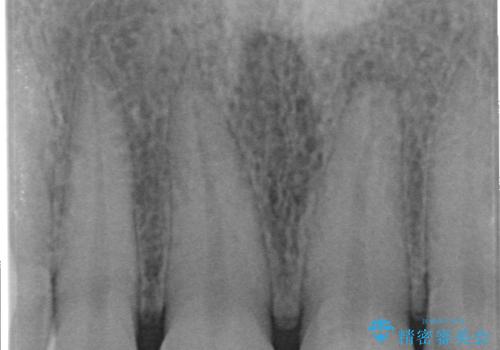

- 右上の前歯が折れたことを主訴に来院された患者様です。

歯が折れた部分は他院により応急処置で仮止めされていました。

欠けた範囲が大きかったため、セラミッククラウンによる補綴治療を行いました。

※左上の前歯(外国で治療されたとのこと)の失活が疑われたためそちらの治療も提案しましたが、ご希望されませんでした。